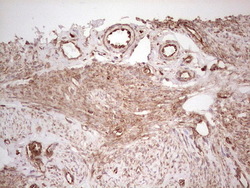

- Submitted by

- OriGene (provider)

- Main image

- Experimental details

- Immunohistochemical staining of paraffin-embedded Adenocarcinoma of Human colon tissue using anti-WIBG mouse monoclonal antibody. (Heat-induced epitope retrieval by 1 mM EDTA in 10mM Tris, pH8.5, 120C for 3min, TA806496)

- Validation comment

- IHC